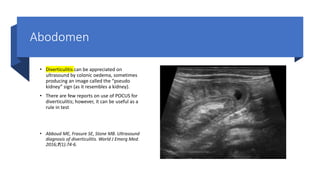

• Diverticulitis can be appreciated on

ultrasound by colonic oedema, sometimes

producing an image called the “pseudo

kidney” sign (as it resembles a kidney).

• There are few reports on use of POCUS for

diverticulitis; however, it can be useful as a

rule in test

• Abboud ME, Frasure SE, Stone MB. Ultrasound

diagnosis of diverticulitis. World J Emerg Med.

2016;7(1):74-6.